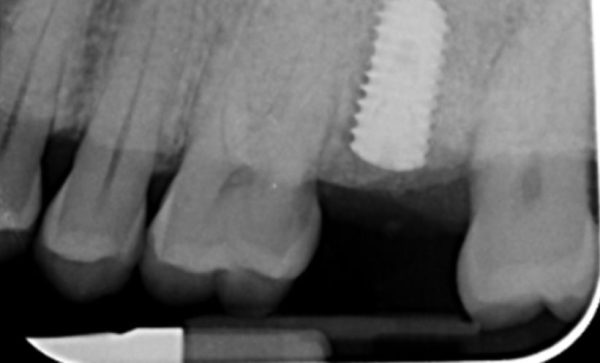

I have been a patient of Dr Verma for 8 years, my treatment has included crowns and an implant. Treatment plans and options are explained to me clearly, my concerns and anxieties are allieviated without hurry or pressure in a gentle and reassuring way. I feel my patient satisfaction is valued.

Sukal has been my dentist for many years, from simple check ups to a dental implant! I have always felt comfortable in the dentist chair and happily watched the TV on the ceiling while work is done on my teeth and never once felt any pain and always felt comfortable. I would never go anywhere else! Thank you all for being kind, caring and helpful at all times :-) Sarah Galloway